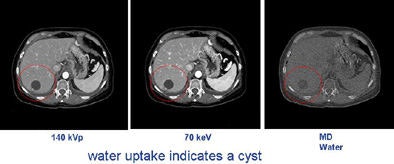

In the hands of researchers, dual-energy analysis of images could potentially help distinguish cysts from cancers and possibly even malignant from nonmalignant lesions in the lungs, colon, solid organs, and blood vessels.

"We have actually subtracted out iodine and water in soft tissues. If you measure the energy, you can actually discern where cysts and cancers are," Smith said.

The interpolation process, performed by the scanner's software, can estimate 101 energy levels that fall between high and low kVp levels pulsed during scanning, Stahre said. The interpolation function is precise, he said, because it is based on known attenuation curves for various materials. Therefore, by comparing the same point on two curves, many materials such as water and iodine can be distinguished, potentially enabling the differentiation of soft tissues. For example, early research has shown that a liver cyst that absorbs water can be distinguished from a tumor, which absorbs iodine.